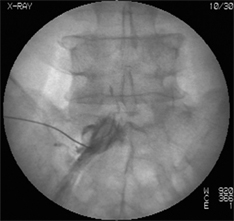

| 神经根造影 | 在数根神经根当中找出病变部位的重要检查项目。在神经根周围注入造影剂后CT扫描。 |

神经根造影